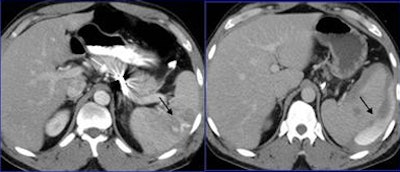

| A 45-year-old man after a car collision (left). Initial axial CT performed after splenic artery embolization (white arrow), shows a round area of increased attenuation in the spleen (black arrow).This finding was believed to represent active bleeding, but organ injury was not visible. Five-minute delayed scan (right) demonstrated intraperitoneal fluid, hematoma, and contrast material extravasation, confirming that the finding was secondary to delayed splenic rupture. The patient subsequently underwent splenectomy. All images and data courtesy of Dr. Alessandro Lemos. |